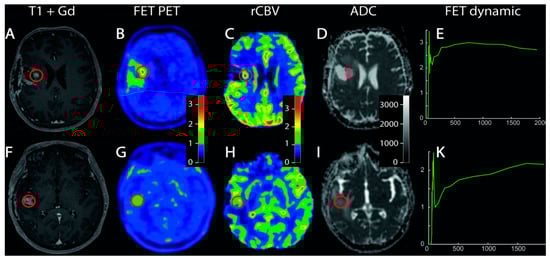

- Pyka, T.; Hiob, D.; Preibisch, C.; Gempt, J.; Wiestler, B.; Schlegel, J.; Straube, C.; Zimmer, C. Diagnosis of glioma recurrence using multiparametric dynamic 18F-fluoroethyl-tyrosine PET-MRI. Eur. J. Radiol. 2018, 103, 32–37. [Google Scholar] [CrossRef]